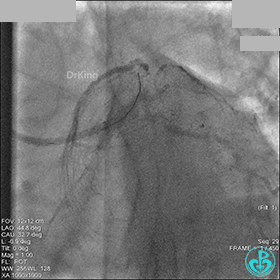

AL 1.0指引导管到位,简单短时尝试导丝不能顺利通过前降支或回旋支病变。改变策略处理右冠脉病变,计划植入2枚支架。AL指引导管到位,Sion blue导丝到达右冠脉远端。导丝通过后1.5mm及2.5mm球囊14~16atm充分扩张中段病变。

右冠脉中段充分扩张后欲植入3.5×38mm支架时,支架难以通过中远段扭曲处,且指引导管、导丝弹出飞扬。反复尝试导丝重新到达右冠脉远端时通过不顺利,局部造影剂滞留,远端血流接近3级。

右冠脉血流3级,患者无症状,终止手术。